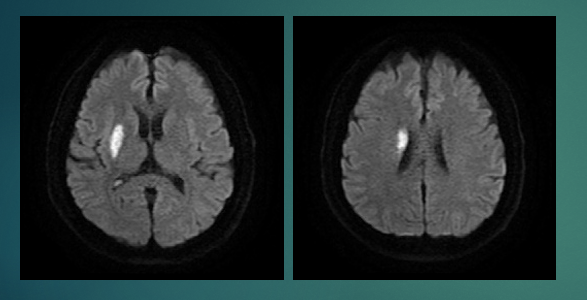

MRI (磁力共振造影) 在診斷超早期缺血性中風敏感度極高

MRI (磁力共振造影) 的擴散加權成像(Diffusion-Weighted Imaging, DWI ) 影像 對缺血性中風非常敏感,為CT的4–5倍。超早期 (hyperacute)缺血性中風是指發病後最初數小時(通常0-6小時)內的階段,此時腦組織正處於最高風險,但若及時介入,仍有極高機會挽救。MRI (磁力共振造影) (DWI),在此階段被公認為最敏感、最準確的診斷工具,能在腦細胞缺血數分鐘內即顯示異常。相反,CT (電腦掃描) 在缺血性中風的超早期時刻,通常都是的呈假陰性(假陰性率高達50%以上)

MRI 在超早期缺血性中風的敏感度

根據多項大型臨床研究及統合分析,DWI-MRI 在超早期缺血性中風的敏感度極高,範圍約 88%–99%,遠高於傳統非對比CT掃描(敏感度僅約39%–64%)。在發病後最初數小時內,DWI 能偵測到腦組織水分子擴散受限的變化,即使梗塞體積很小(低至0.15–0.6 mL)也能清晰顯示。

- 發病後數分鐘至6小時:DWI 敏感度約88–97%,部分研究達99%。

- 與CT比較:CT 在超早期常呈陰性(假陰性率高達50%以上),而 MRI (DWI) 敏感度為CT的4–5倍。

- 特異度:DWI 特異度亦高達92–100%,能有效排除非缺血性病變(如腫瘤、炎症或偏頭痛)。